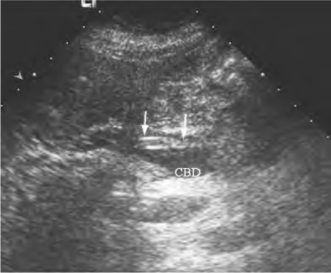

1.肝外胆管扩张,在扩张的胆管内可见双线状强回声,中心为无回声,呈“等号”状(图25-17),又称“通心面”征,横切面呈“同心圆”状。如蛔虫尚存活,可见其蠕动。

图25-17 胆管蛔虫声像图

扩张胆管内见“等号样”强回声(箭头所示)